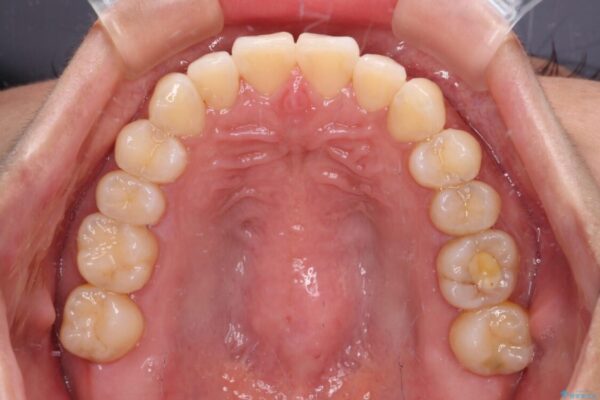

前歯のデコボコで前方に出ていることを気にして来院された患者様です。

上顎前歯が捻れて前方に飛び出しており、下顎前歯もそれに沿うようにデコボコとなっていました。

IPR(歯と歯の間を削る処置)によりスペースを獲得して上下顎前歯のデコボコを改善し、飛び出している前歯が引っ込むように設定し、インビザラインにて矯正治療を行うこととしました。

治療前

• 【モニター】前歯のデコボコをインビザラインで改善 治療前画像